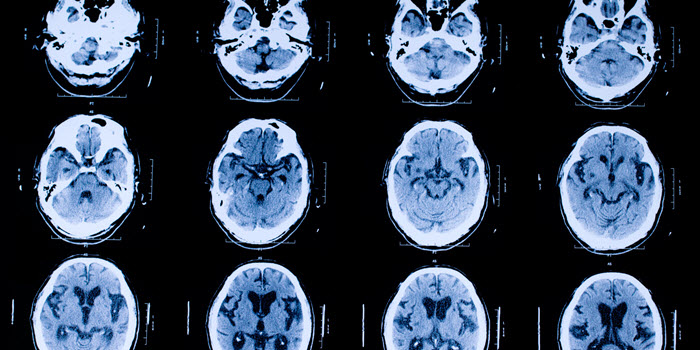

- Рентгенография, МРТ, КТ черепа – визуализирующие методики.